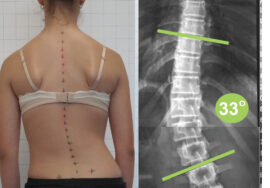

يعاني العديد من الأشخاص من اعوجاج العمود الفقري، وهو انحناء غير طبيعي يؤثر على شكل الظهر ووظائفه. يمكن أن يؤدي هذا الانحناء إلى آلام مزمنة ومشكلات في الحركة اليومية، إلا أن العلاج الطبيعي يُعد من الوسائل الفعالة لتقليل الأعراض وتحسين وضعية الجسم دون تدخل جراحي.

في حالات الاعوجاج البسيطة أو المتوسطة، يمكن للعلاج الطبيعي أن يمنع تطور الانحناء ويُحسن الأداء البدني دون الحاجة إلى تدخل جراحي. أما في الحالات المتقدمة، فيُستخدم العلاج الطبيعي لتقوية الجسم قبل الجراحة أو لدعم الشفاء بعدها.